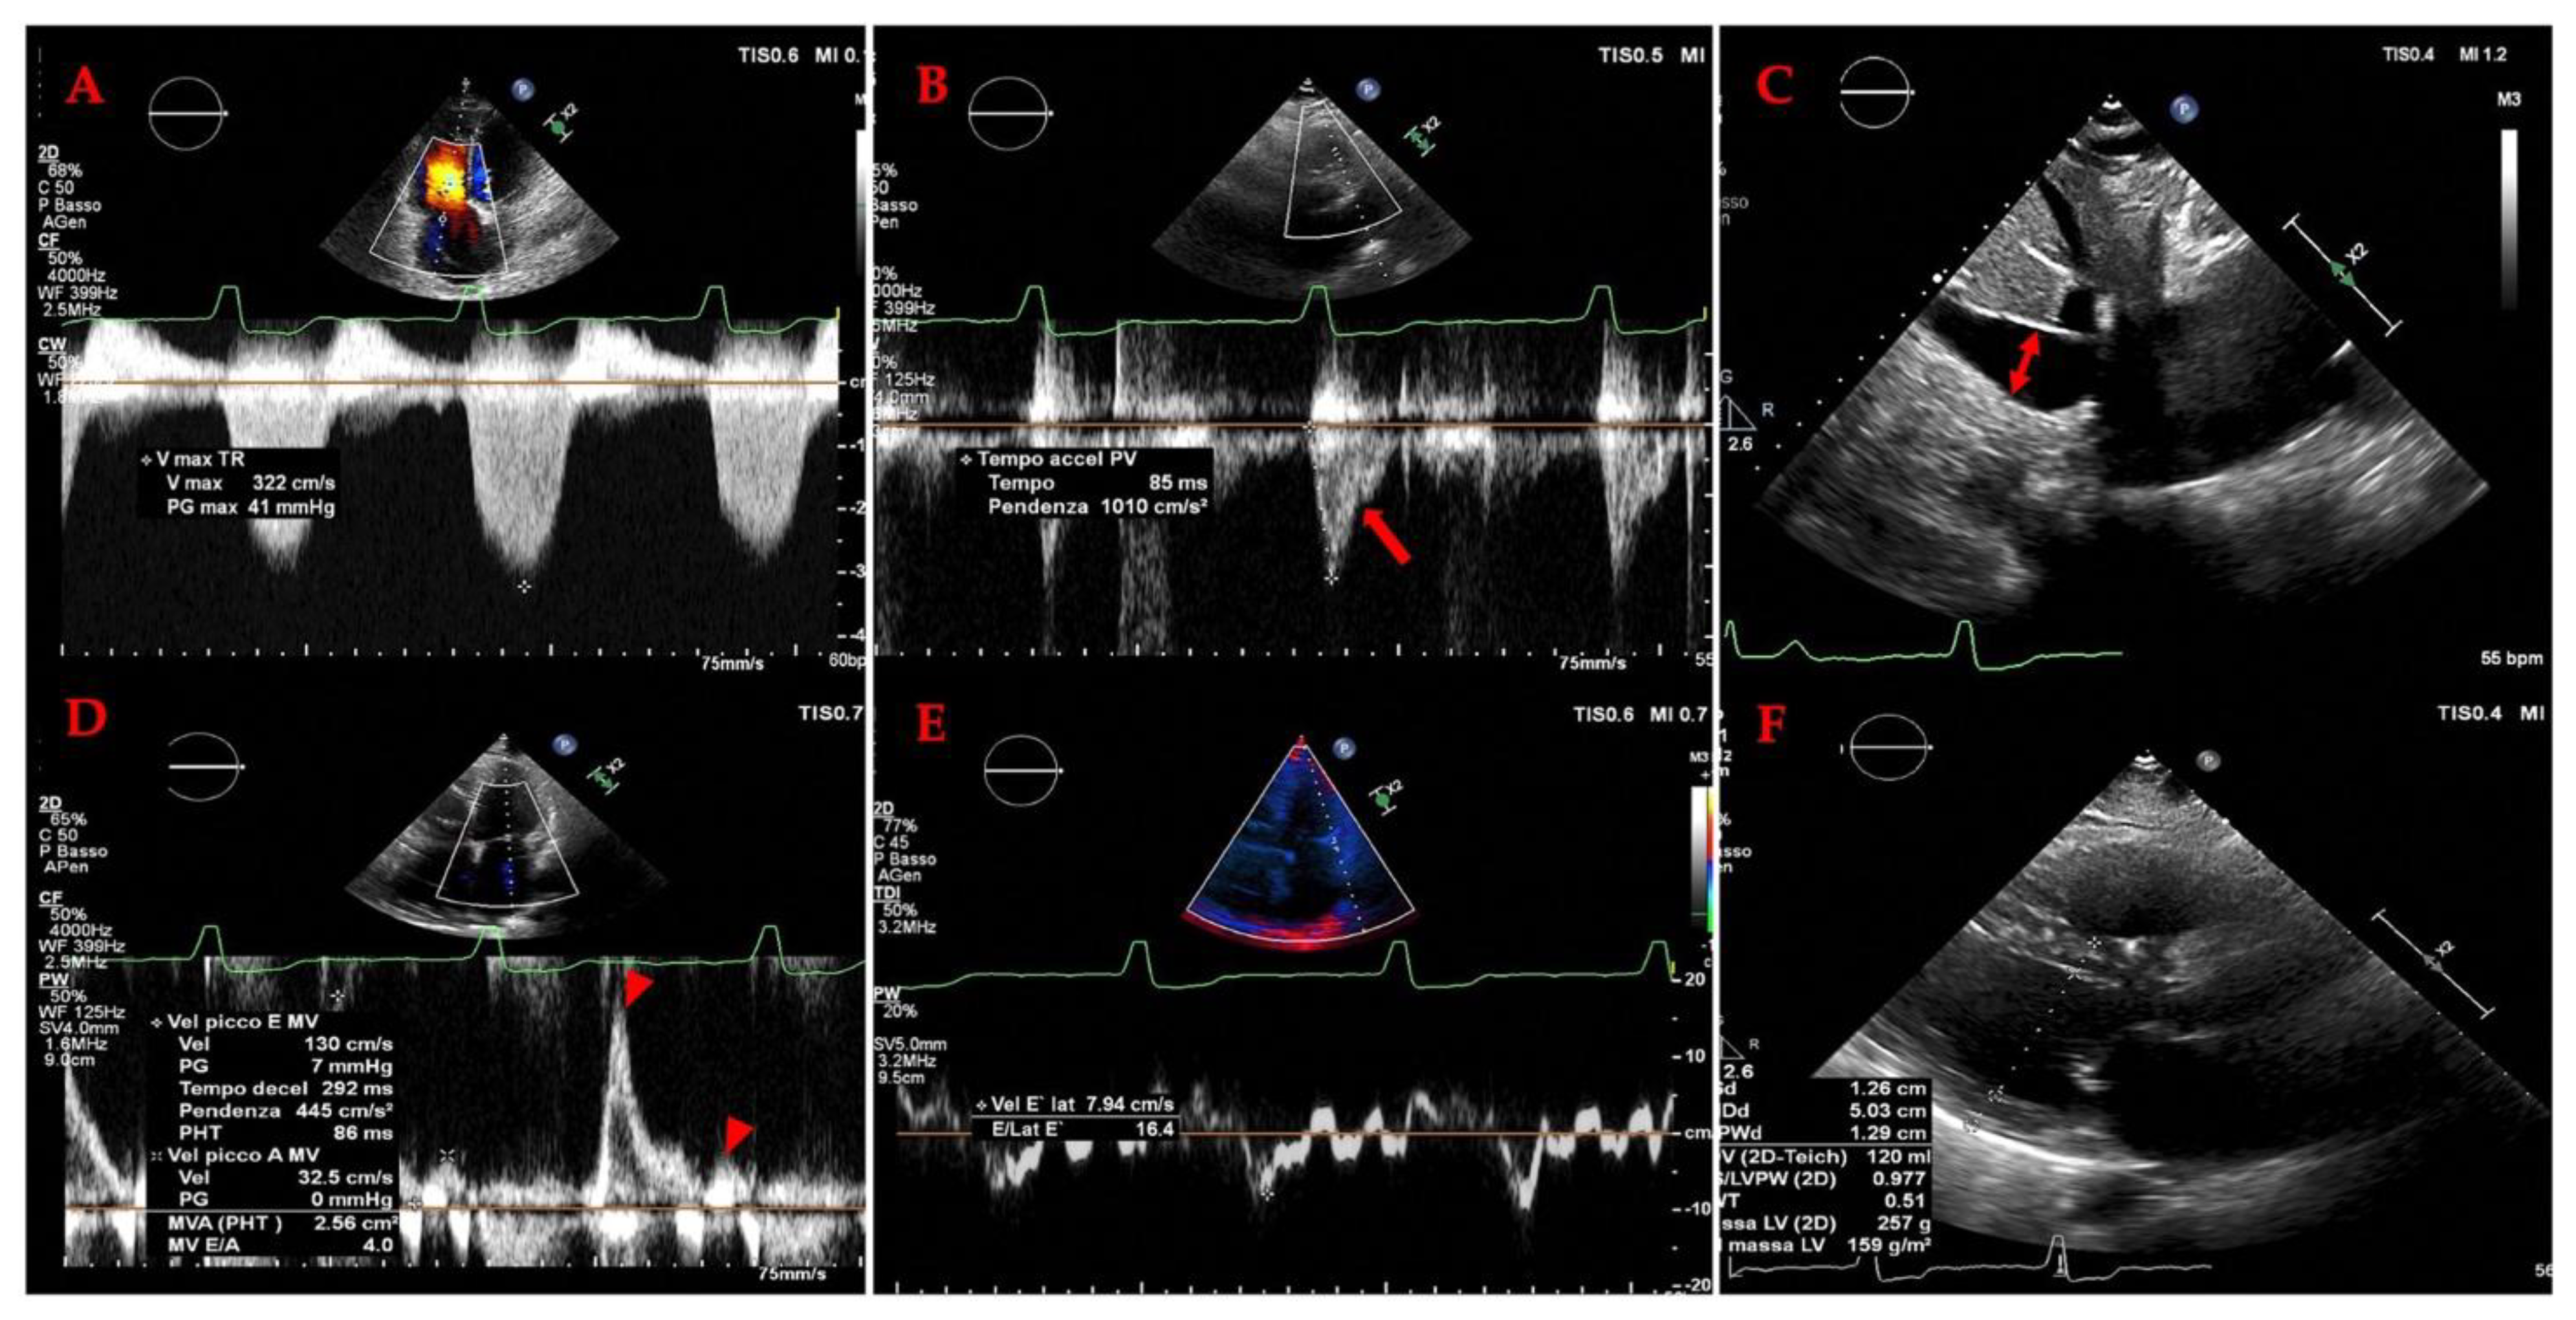

4.2. Cardiac Evaluation: Echocardiography

4.2.1. The Evolving Role of Echocardiography OF LEFT HEART in Heart Failure

4.2.2. The Evolving Role of Echocardiography in Heart Failure: A Focus on the Right Heart and Pulmonary Hypertension (PH)